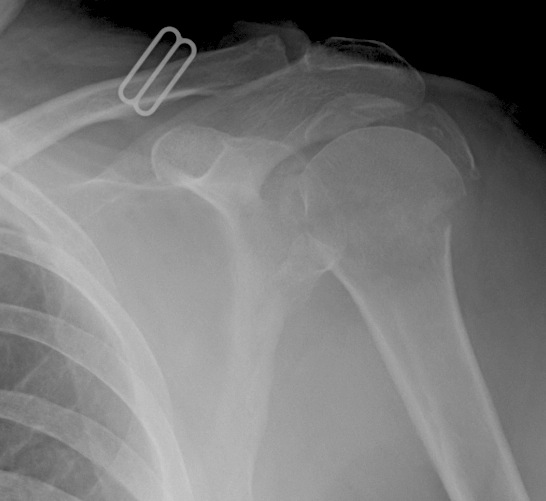

hertel criteria